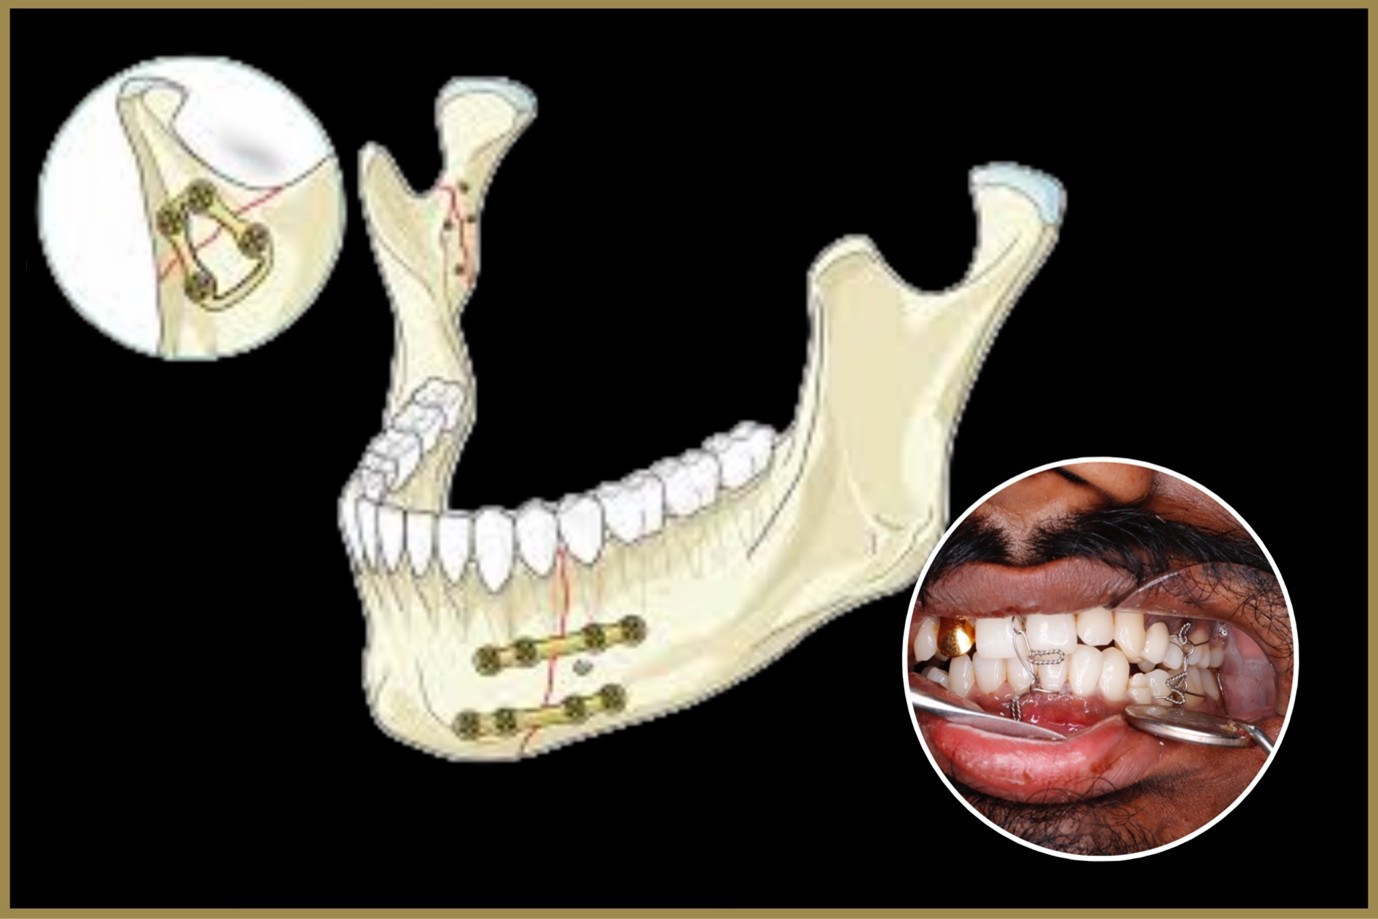

Sometimes, achieving the perfect smile requires more than braces or aligners — and that’s where surgical orthodontics plays a vital role. At Elite Dental Care and Aesthetics, we use advanced orthodontic surgery techniques to correct complex jaw irregularities and help patients achieve balanced facial aesthetics, proper bite alignment, and confident smiles.

Surgical orthodontics, also known as orthognathic surgery, is performed to realign the jaws when they do not meet correctly or when orthodontic treatment alone cannot correct the problem. It not only improves dental function but also enhances facial harmony and overall appearance.

What Does the Surgical Orthodontic Procedure Include?

Comprehensive Evaluation – Detailed digital imaging and 3D scans to assess jaw structure, bite alignment, and facial balance.

Treatment Planning – Collaboration between orthodontist and oral surgeon to design a customized surgical and orthodontic plan.

Surgical Correction – Precision surgical adjustments are made to reposition the upper, lower, or both jaws into proper alignment.

Post-Surgery Orthodontics – Braces or aligners are used after surgery to fine-tune teeth positioning and ensure a perfect bite.

Follow-Up Care – Regular monitoring to track healing, ensure stability, and maintain long-term results.

Benefits of Surgical Orthodontics

Improved Functionality – Corrects chewing, speaking, and breathing difficulties caused by jaw misalignment.

Enhanced Facial Aesthetics – Balances facial proportions for a naturally symmetrical appearance.

Permanent Results – Offers lasting correction of structural jaw problems.

Boosted Confidence – A beautifully aligned smile enhances self-esteem and facial appearance.

Comprehensive Correction – Addresses both functional and cosmetic concerns for a complete transformation.

At Elite Dental Care and Aesthetics, we combine precision, expertise, and advanced technology to ensure safe and effective results. Each treatment is carefully tailored to your needs, restoring not just your smile but also your confidence.

With surgical orthodontics, you can achieve a balanced bite, improved facial harmony, and a healthier, more radiant smile that lasts a lifetime.